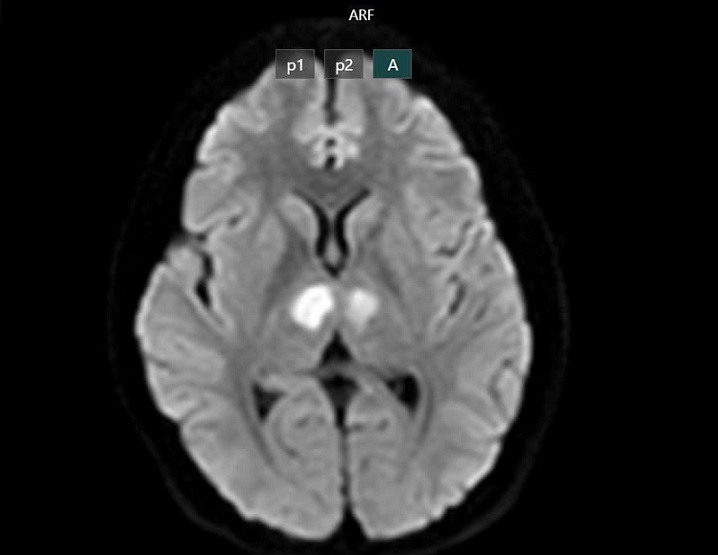

Cụ thể, khoảng 16h ngày 21/2 bệnh nhân vẫn nói chuyện với con, nhưng đến khoảng 19h30, gia đình phát hiện bệnh nhân trong trạng thái bất tỉnh, gọi hỏi không đáp ứng. Bệnh nhân không sốt, không co giật, không nôn. Người nhà đưa bệnh nhân đến bệnh viện tư để cấp cứu. Kết quả chụp MRI cho thấy não bệnh nhân có hình ảnh tổn thương vùng đồi thị hai bên. Gia đình xin chuyển bệnh nhân sang Bệnh viện Bạch Mai để được tiếp tục điều trị.

Phim chụp cho thấy não bệnh nhân bị tổn thương vùng đồi thị hai bên